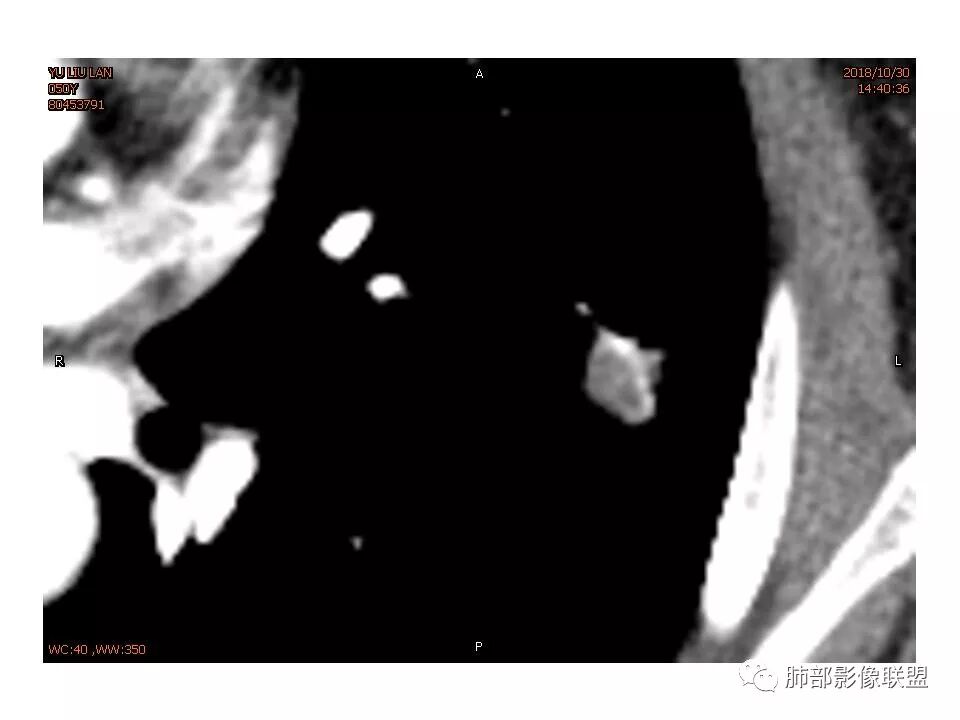

女,50。实性不规则结节,大小12*13mm,分叶、毛刺、胸膜凹陷,牵拉力强,增强渐进性强化,动脉期强化20,静脉期还有进一步强化。边缘强化,点状坏死。

其内血管被破坏。

女性,50岁。U型凹陷、平直征

南边:支持炎性

1.胸膜下略不规则实性密度结节影,孤立,缺乏典型深分叶,可见淡薄边界模糊磨玻璃晕,可见相对细长软毛刺。

2.如南边老师分析,病灶缺乏边缘膨隆优势,甚至部分平直内收。

3.病灶收缩力不强,整体强化程度不显著。

4.综上,病灶更符合炎性,如隐球菌感染等,而不大符合肺腺癌。具体到机化性肺炎略有些出乎预料。